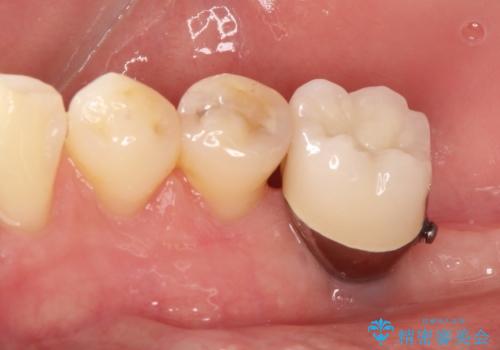

- 奥歯が破折していたため、抜歯を行ったあとインプラントを埋入して咬合回復を行っております。

- 40万円費用は治療当時の料金となります